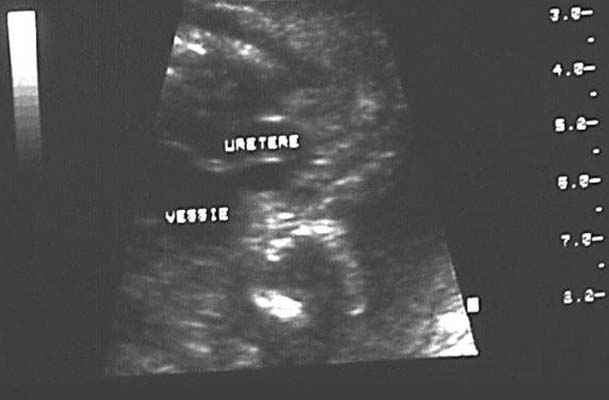

Dilatation urétérale : Structure tubulée à contenu anéchogène, rectiligne ou tortueuse, pouvant présenter des variations de calibre en rapport avec le péristaltisme.

*Obstacle de la jonction urétéro-vésicale :

- Méga-uretère primitif congénital

- Abouchement ectopique avec ou sans urétérocèle (dilatation kystique de l’extrémité distale de l’uretère au sein de la lumière vésicale). Sont associés dans la moitié des cas à une duplication de la voie excrétrice.

- Reflux vésico-urétéral (La variabilité avec le temps et la visualisation de l’uretère ou la majoration de la dilatation au cours d’une miction sont en faveur d’un reflux)